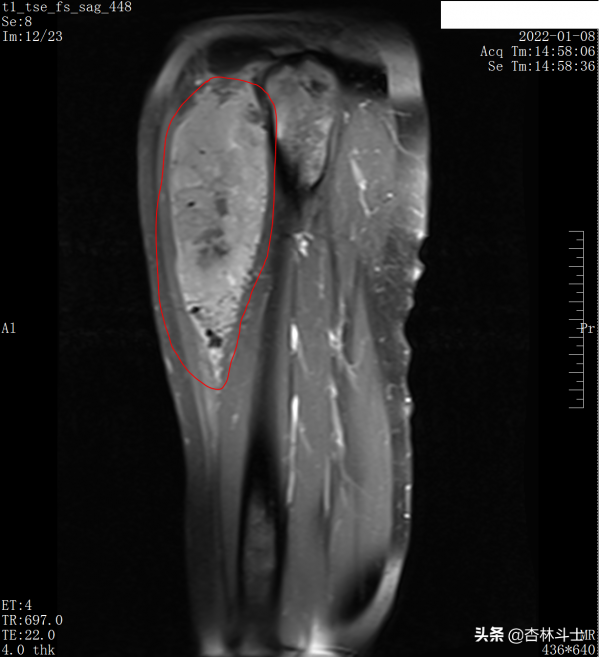

入院後查了左大腿3T磁共振平掃+增強,如圖示:

pd-tse 矢狀位-壓脂序列,可見股骨上段前方巨大類似橢圓形以高訊號為主混雜訊號影,內可見流空血管(藍圈)